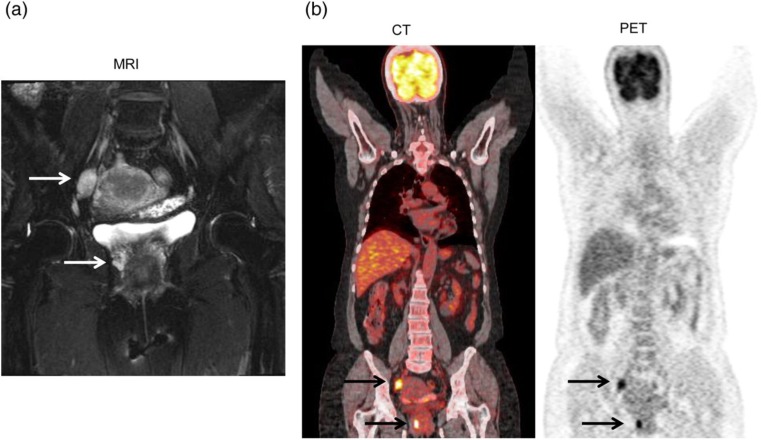

宫颈恶性黑色素瘤是一种罕见的皮肤外黑色素瘤,其发展积极,预后黯淡。据我们所知,之前没有发表的报告讨论过18F-FDG正电子发射断层扫描/计算机断层扫描(PET/CT)在治疗这种疾病中的作用。我们的病例研究涉及一名66岁的宫颈恶性黑色素瘤妇女。患者接受了PET/CT检查,发现了MRI未检测到的转移和病变。连续PET/CT显示,该疾病最初局限于骨盆,但随后转移到腹部主动脉旁淋巴结,随后广泛转移到脑、肺、乳房、锁骨上、颈部和其他腹部淋巴结,随访6个月。PET/CT用于补充传统的解剖成像方式,为全身筛查提供了一种新的方式。不确定病变的代谢活动可视化可能有助于这种罕见疾病患者的分期、再分期、治疗计划和预后预测。

Malignant melanoma of the uterine cervix is a rare extracutaneous melanoma which develops aggressively and is associated with a bleak prognosis. To our knowledge, no prior published reports have discussed the role of 18F-FDG positron emission tomography/computed tomography (PET/CT) in managing this disease. Our case study involved a 66-year-old woman with a malignant melanoma of the uterine cervix. The patient received PET/CT that identified metastases and lesions which had not been detected from her MRI. Serial PET/CT elucidated that the disease was initially limited to the pelvis, but then metastasized to the abdominal para-aortic lymph nodes, followed by extensive metastases to the brain, lungs, breast, supraclavicular, neck, and other abdominal lymph nodes, as observed at 6-month follow-up. PET/CT was used to complement conventional anatomic imaging modalities, and provided a novel modality for whole body screening. Visualization of the metabolic activity of indeterminate lesions may help in staging, re-staging, treatment planning, and prognostic prediction for patients with this rare disease.